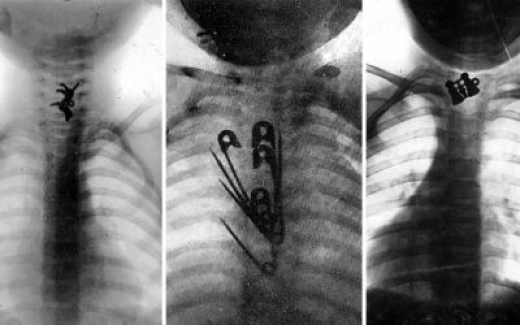

Бұған дейін Астана қаласындағы №2 Қалалық балалар ауруханасында жыл басынан бері балалардың ағзасынан тиын, ине, магнит, ойыншық және тағы да басқа ірілі-ұсақты 159 бөгде заттар шығарылғанын жазған болатынбыз.

«Бөгде заттар баланың ағзасына көбінесе құлақ, мұрын, ауыз арқылы түседі. Тыныс алу жолдары арқылы кірген зат мұрын ішінде, кеңірдекте, өкпе тінінде тұрып қалуы мүмкін. Ең қауіпті жер – көмей мен кеңірдек. Тез арада медициналық көмек көрсетілмеген жағдайда бала ауа жетпегендіктен арада 1-2 минут өтпей-ақ көз жұмуы мүмкін», - дейді ол.